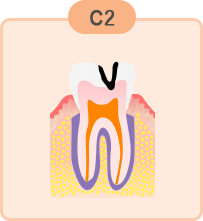

中度のむし歯

象牙質までむし歯が進んだ状態です。